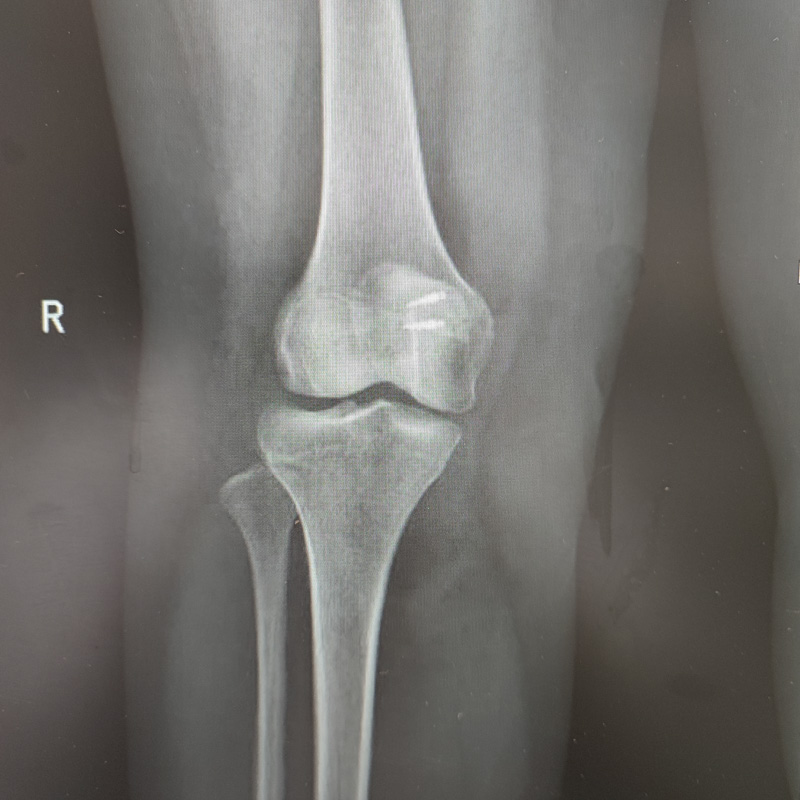

▲髕骨復位,髕股關節關系良好

經過三個月的康復鍛煉,王先生的膝關節屈曲已達120°,近日再次到醫院復查時,便發生了文章開頭那一幕,醫護人員也為王先生能夠擺脫病痛困擾回歸正常生活而感到高興。